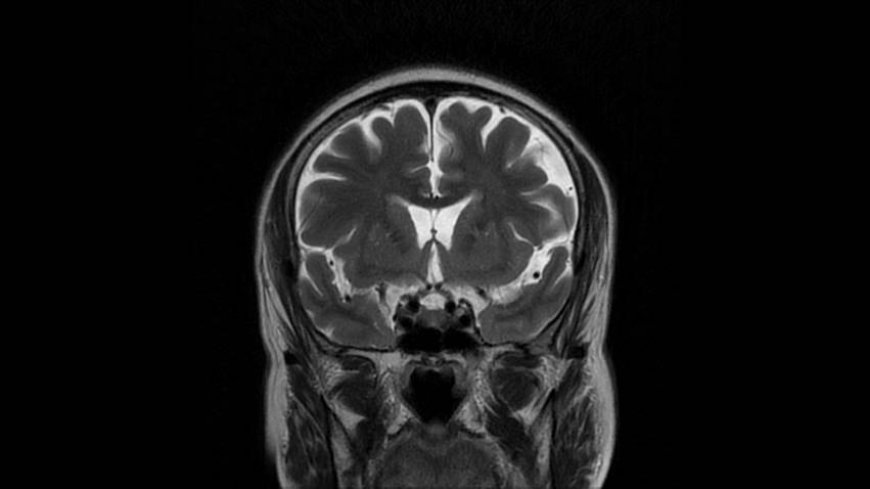

MRI of Brain

Coronal T2